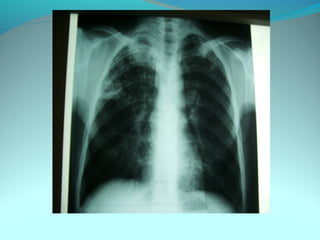

Cliché normal